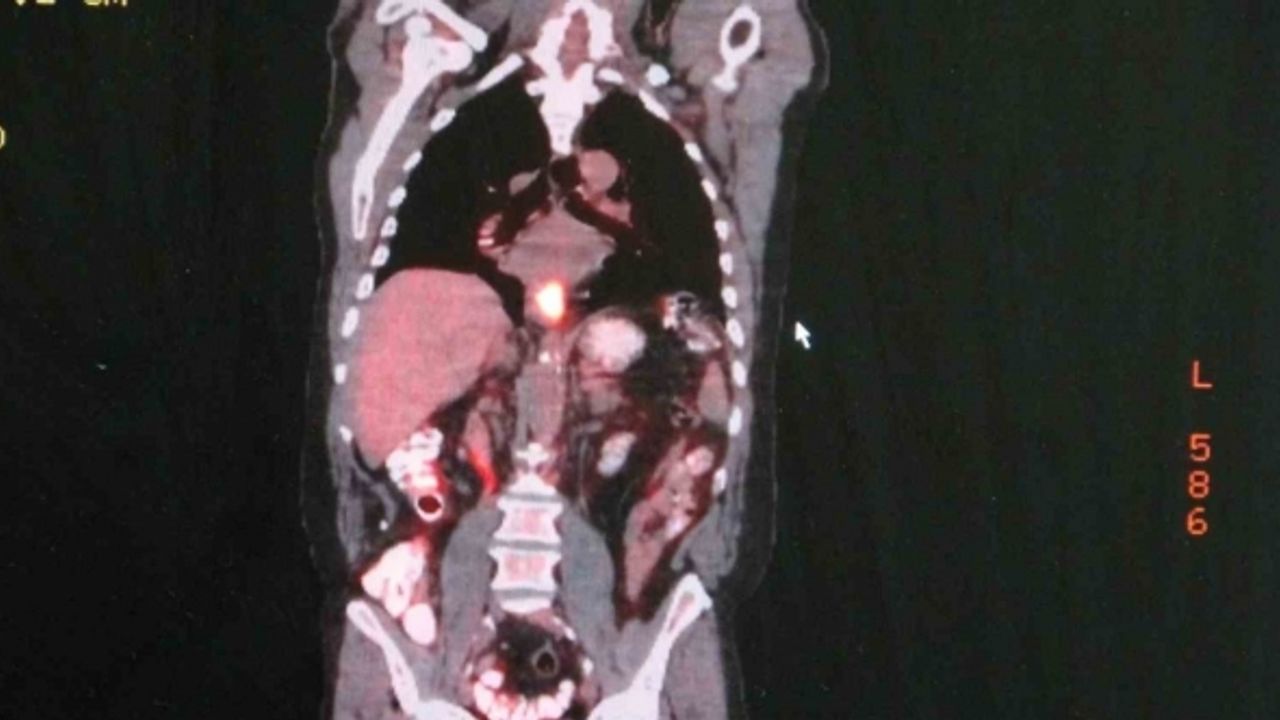

Artan yemek borusu kanseri vakalarının ardından hastalıkla alakalı uyarılarda bulunan Ermerak, "Yemek borusu kanseri dünyada 9. sırada en sık görülen kanser tipidir. Ve çok sinsi seyreden bir hastalıktır. Geç bulgu ve şikayet verdiği için genelde hastalar erken evrede fark edemezler. Hastaların sadece yüzde 25’ini diğer organlara sıçramadan yakalayabiliyoruz. Hastalar bu kansere erken evrede yakalandıklarında sağ kalımları yükseliyor. Bu hastalığın semptomları; yutma güçlüğü, yemek yerken takılma hissi, istemsiz kilo kaybı, öksürük, göğüs, iman tahtası ve sırtta özellikle yemek sonrası gelen bir ağrı ve bu gibi şikayetlerle hastalar mutlaka ilgili merkeze başvurmalılar. Erken evrede teşhis hastaların tedavi şansı artmaktadır." dedi.